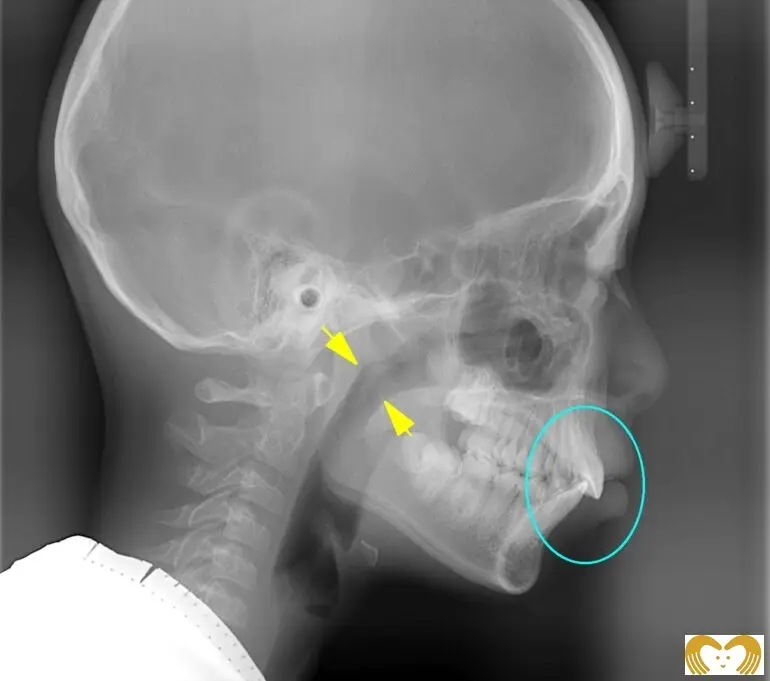

症例03:出っ歯

《Before》《After》

- 年齢:

- 8~12歳

- 性別:

- 男の子

- 治療内容:

- ネオキャップシステムによる、上顎前突(出っ歯)の治療。矯正前後のレントゲン比較から、気道(黄色矢印部分)が広くなっていることがわかります。現在は、当初見られた口呼吸も改善され、自然と鼻呼吸ができるようになりました。

- 治療回数・期間:

- 約4年間

- 治療費:

- 495,000円(税込)

- リスク:

- 取り外し可能な装置の為、治療の効果が使用頻度に左右されます。